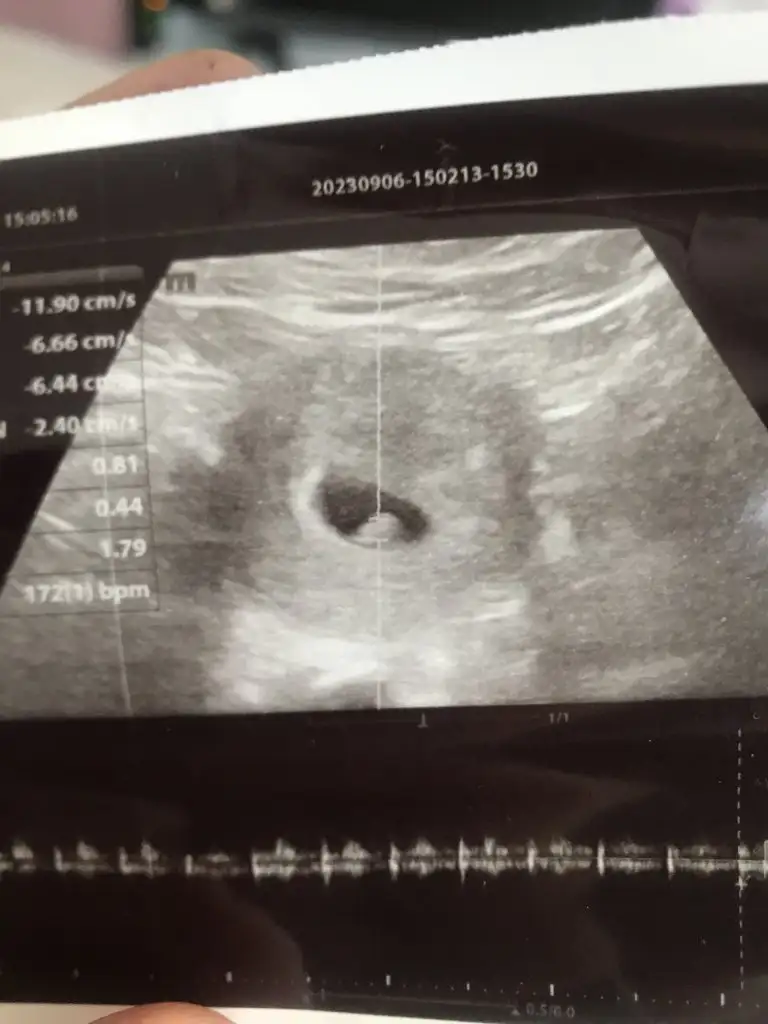

Bizede tahmin yapar mısınız 6+6 gunlukken çekildi VAJİNAL USG